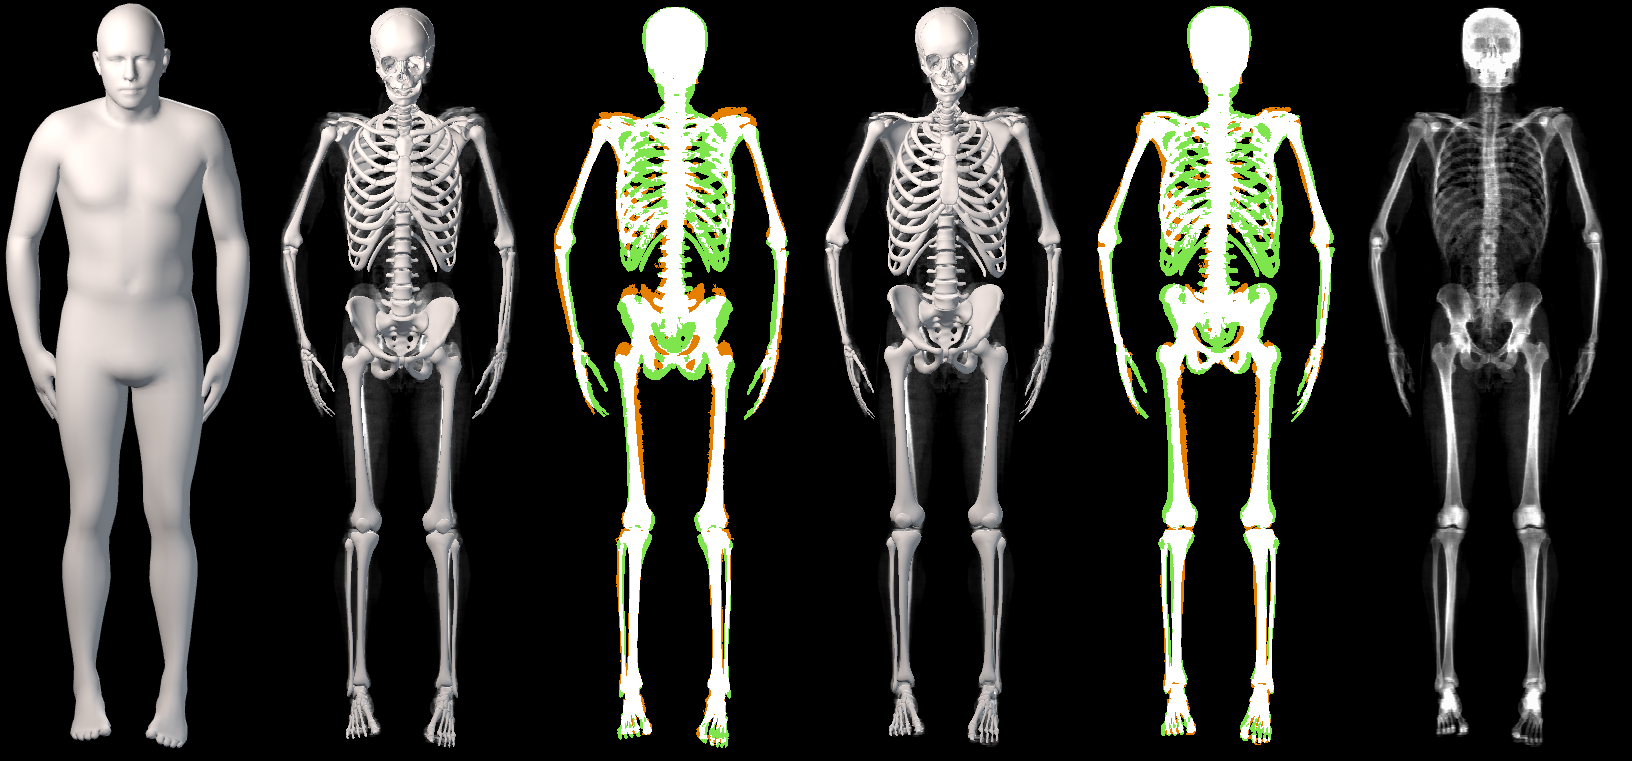

In this work, we address the problem of inferring the human anatomic skeleton, i.e. the bone shapes and locations, solely from surface observations. That is, we infer the bones from the skin. To that end, we learn a statistical model of the skeleton shape and its correlation with the skin surface (Fig. 1 left). Given a posed body, our method predicts the skeleton from the body shape, and poses it inside subject to anatomic constraints (Fig. 1 right).

Unfortunately, DXA does not produce 3D data. Consequently, we fit the STAR body model to the soft-tissue image to obtain an estimate of the outer 3D body surface. We also employ a constrained part-based fitting method to fit bones to the DXA bone image. These then provide pairs of inside and outside data for training. We use 1200 male and 1200 female DXA images from UK Biobank [36], which we split into training and evaluation sets. From the training set we learn skeletal shape variation and the mapping from outside to inside. Given a new body shape and pose, OSSO reposes the body to a canonical pose and predicts the skeleton inside. It then reposes the skeleton to the input pose, subject to various anatomic constraints. With ground truth DXA scans, we validate the reposing in lying down poses and show that OSSO outperforms Anatomy Transfer [1]. We also demonstrate the use of OSSO by estimating skeletons for a variety of body shapes and poses.

The presented metric has a limitation: predicting all the skin volume as bone would obtain a perfect result (, ). In Fig. 4 and Sup. Mat. we show that visually, OSSO’s predictions are coherent and match the DXA bone images better than Anatomy Transfer. In Sup. Mat. we provide examples of subjects with high Body Mass Index, for which Anatomy Transfer predicts a stretched skeleton, while ours are closer to the DXA skeleton mask.

5.4 Generalization to new poses